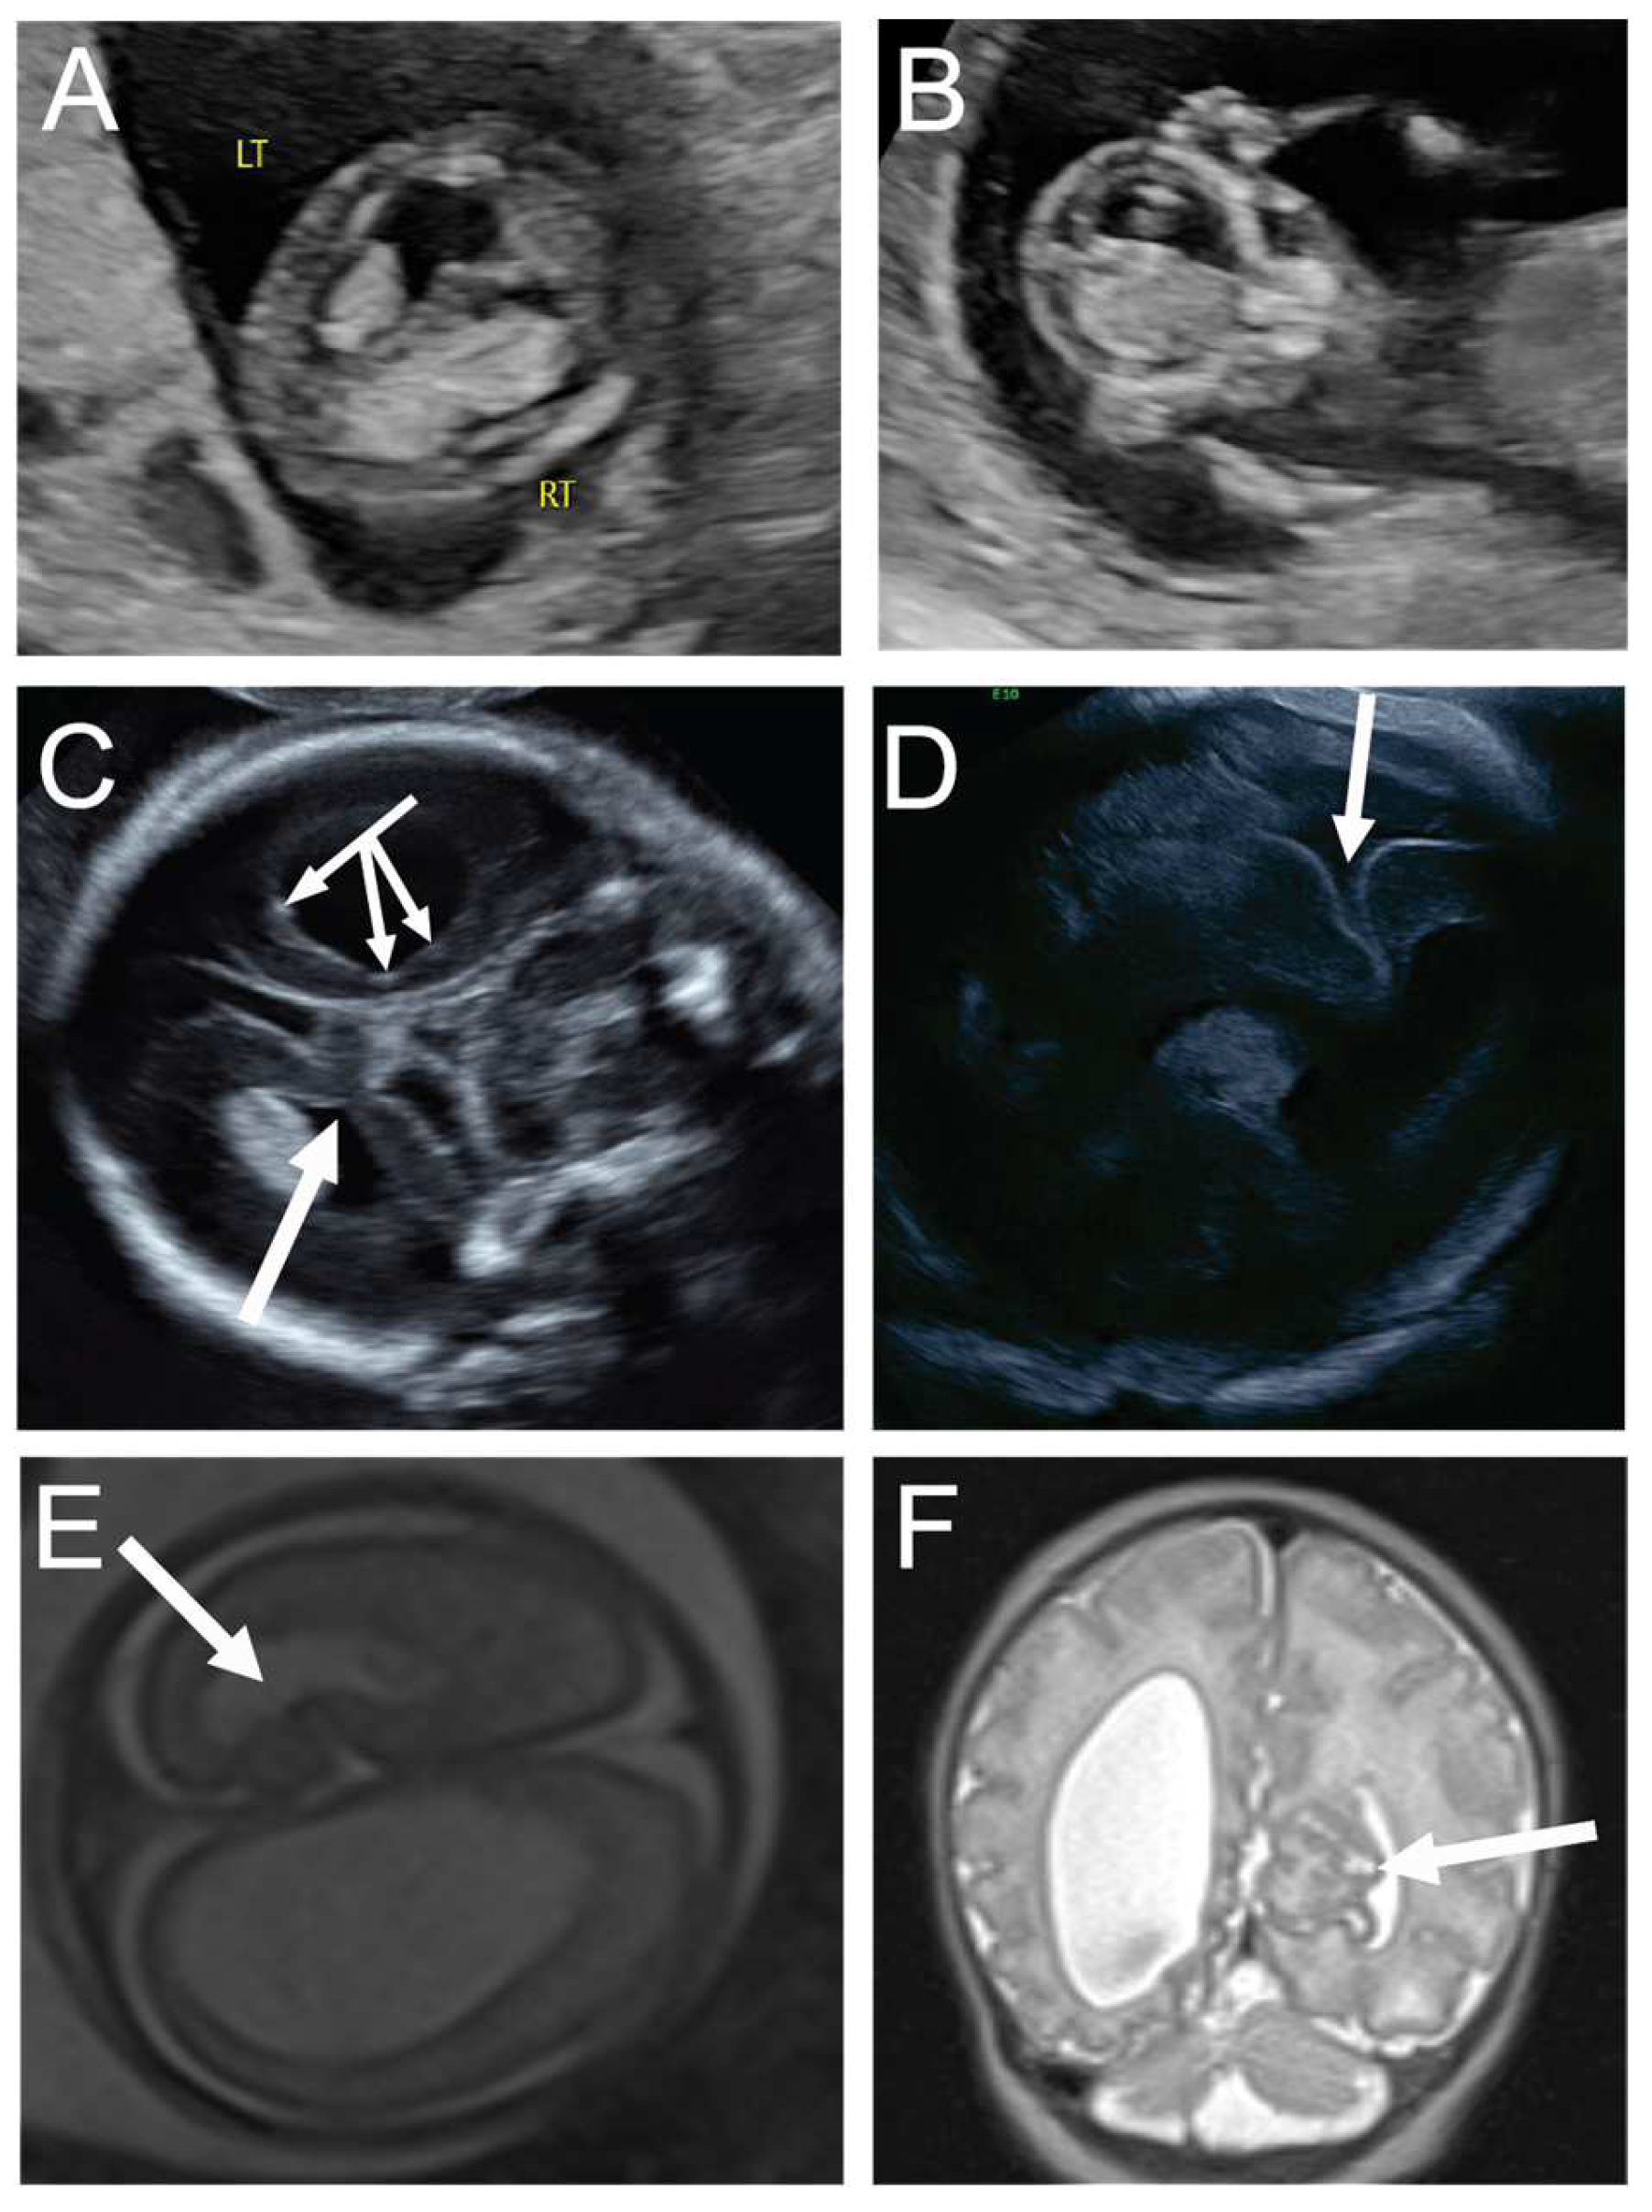

Figure 2. A 31-year-old G3P1 at 13 weeks and 1 day’s gestation was seen for first-trimester screening, and the fetus was noted to have an irregular, asymmetrically enlarged and mottled right choroid plexus, concerning for possible early right intraventricular hemorrhage and ventriculomegaly, note Rt = right side of fetus and Lt = left side of fetus (A,B). Maternal serum infectious and neonatal alloimmune thrombocytopenia workups were negative. Neurosonogram at 20 weeks and 0 days demonstrated the same severe unilateral right ventriculomegaly with stippling along the lining of the right ventricle, consistent with germinal matrix hemorrhage versus heterotopia (triple headed arrow, (C)), with additional findings of right periventricular white matter loss and a contralateral focal area of abnormal folding of the left mesial cortex, concerning for cortical dysplasia or polymicrogyria (single arrow, (C)). Fetal MRI confirmed right unilateral ventriculomegaly with evidence of right germinal matrix and intraventricular hemorrhage, as well as cortical abnormality in the left mesial occipital lobe (arrow, (E)). The mother opted to continue the pregnancy and declined amniocentesis. Ultrasound at 26 weeks and 5 days’ gestation showed progressive right ventriculomegaly with midline shift and continued prominence of contralateral cortical dysplasia, with possible progression to schizencephaly (arrow, (D)). She was delivered via cesarean at 36 weeks in the setting of preterm labor. Postnatal MRI demonstrated worsening of the cortical maldevelopment in the left mesial occipital lobe (arrow, (F)), a few scattered foci of periventricular nodular heterotropia, and abnormal vertical and shallow appearance of the right sylvian fissure. At two years of age, the child was meeting developmental milestones.

In the second case, intraventricular hemorrhage was suspected on first-trimester ultrasound. Monitoring progression throughout the trimesters was possible on ultrasound, and it revealed not only significant ipsilateral cortical volume loss with severe unilateral ventriculomegaly but also the unanticipated finding of contralateral cortical dysplasia, consistent with cortical dysplasia or polymicrogyria, without evidence of volume loss. These findings support the theory that perinatal ischemia from vascular disruption can lead to schizencephaly and cortical dysplasia [9] and may impact contralateral cerebral cortex. Given that the findings suggest perinatal ischemia/vascular disruption, potentially causative genetic etiologies such as COL4A1, COL4A2, JAM3, and TREX1, should be considered and are best evaluated with whole-exome sequencing.